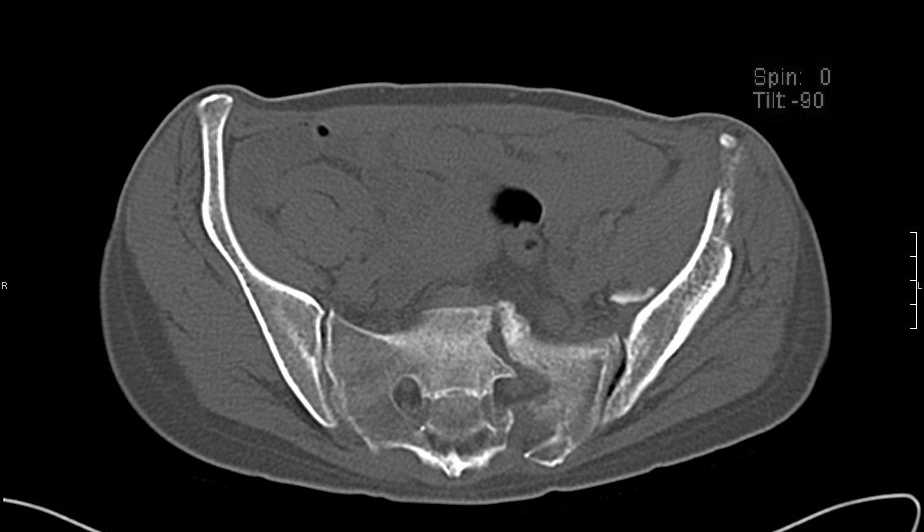

Перелом свода и основания черепа. Вертикально-нестабильное повреждение таза, осложнённое разрывом мочевого пузыря. Чрезвертельный перелом левого бедра. Перелом правой таранной кости, переломовывих правой кубовидной кости. Тупая травма живота, разрыв печени, ушиб почек. Забрюшинная гематома. В день травмы - лапаротомия, ушивание ран печени. Разрыв мочевого пузыря не диагностирован. Течение болезни осложнилось развитием мочевого затёка и обширной пред- и забрюшинной флегмоны, сформировался свищ мочевого пузыря. 19.8.2008 вскрытие, дренировние флегмоны, ревизия мочевого пузыря, обтурация мочевого свища (свищ закрылся в октябре), 1.10.2008 некрэктомия, пластика по Шеде-Лидскому правой кубовидной кости. По результатам КТ диагностирован рак правой почки (диагностическая находка), 8.10.2008 нефрэктомия справа.

Имеется вертикальное смещение левой половины таза с выраженным отведением крыла (клинически подвижности нет), несросшийся низкий двухколонный перелом левой вертлужной впадины с потерей конгруэнтности, укорочение около5 см, застарелый разрыв лонного сочленения, неправильно сросшиеся переломы обеих ветвей правой лонной кости с укорочением, патологическая подвижность лоно-седалищного фрагмента слева. Правая нижняя конечность неопорна, несмотря на то, что лежа прямую ногу поднимает, ходит на левой ноге (ортопедическая обувь) с костылями, справа тазобедренный ортез. Седалищные нервы работают. Урологи отпустили больную на 6 мес.